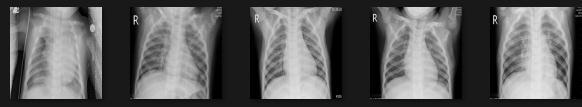

In most cases, the ranges of symptoms of pneumonia andtheCovid 19virusarethesame.Bothareinfectionsof the lungs. Hence, the dataset consists of three separate datasetsofX raysofthechest(COVID 19patients,normal people,andpneumoniapatients).Thereare300photosin all(100COVID 19images,100pneumoniaimagesand100 healthy images). After that, the datasets are divided into two sections: training and testing the classifiers. Fig 1,2,3 showsanexampleofchestX rayimagecollections. Fig.1.

Fig.3.NORMALchest

Rayimages